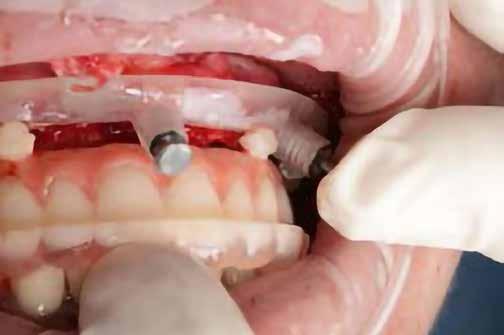

A behelyeztt implantátum primer stabilitását megfelelőnek ítéltük (kb. 40 Ncm) az azonnali terheléshez (9. kép).

Az extrakciót megelőző szituációs lenyomat alapján gyári, titán, ideiglenes abutment felhasználásával, a szék mellett készített, csavaros rögzítésű, azonnali akrilát ideiglenes koronával láttuk el, melyet 20 Ncm nyomatékkal rögzítettünk (10. kép). Az azonnali terhelés szabályainak megfelelően, az ideiglenes korona nem volt kontaktusban a szomszédos és az antagonista fogakkal.

6. kép: Implantátum-ágy preparáció. 7. a–b. képek: Implantátum behelyezés. 8. kép: A behelyezett implantátum. 10. a–b képek: Azonnali ideiglenes korona készítése. 9. kép: Megfelelő primer stabilitás.